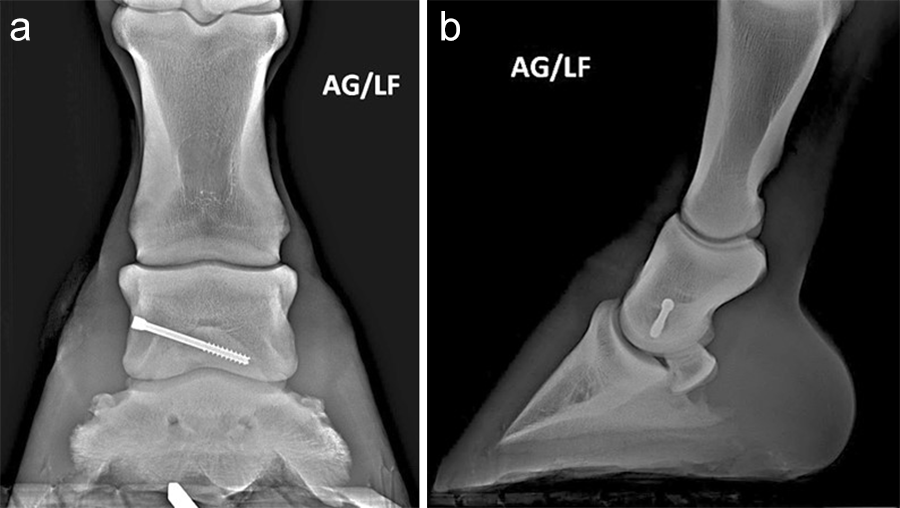

Postoperative radiographs showed accurate screw positioning (Fig 9). The horse was box-rested for 2 weeks and hand-walked for another 6 weeks. Ridden work was resumed after 2 months. The horse remained sound in the postoperative period. Four months after surgery, the radiographic definition of the cyst margins was markedly decreased.

A subchondral middle phalanx bone cyst was identified on a clinically sound 3-year-old Warmblood Gelding during radiographic screening. The osseous lesion was located at the medial and distal aspect of the middle phalanx on the left front limb. Radiographs indicated mild sclerosis of the trabecular bone surrounding the cyst. A magnetic resonance imaging examination confirmed discrete communication with the distal interphalangeal joint (Fig 6). The treatment of choice was surgery, which included placing a cortical lag screw or compression screw across the subchondral bone cyst. This technique aims to promote new bone formation by altering the biomechanical bone environment. A 4.5 mm headless compression screw was placed across the cyst with the veterinary screw targeting clamp.

A 1.6 mm guide wire was advanced through the bone to assess the correct positioning of the targeting clamp. The guide wire is centered within the cyst. At this stage, the ideal screw length was measured on the perioperative radiographs. When using these headless cannulated compression screws, remember that the shaft thread length is approximately 40% of the screw length. Ideally, the threaded shaft of the screw is positioned on the trans-side of the cyst. The 3.2/1.6 mm insert sleeve was then removed and the bone was drilled with a cannulated 3.2 mm drill bit to the required length (Fig 8a). Considering the high-bone density at this location, the entire length of the drill hole was tapped by hand with a cannulated 4.5 mm tap through the 4.5 mm drill sleeve. Next, a 4.5 mm headless compression screw was inserted through the 4.5 mm drill sleeve and tightened by hand (Fig 8b). The stab incision was closed routinely. The horse was covered with a two-layer bandage. The total surgery time was 30 minutes.